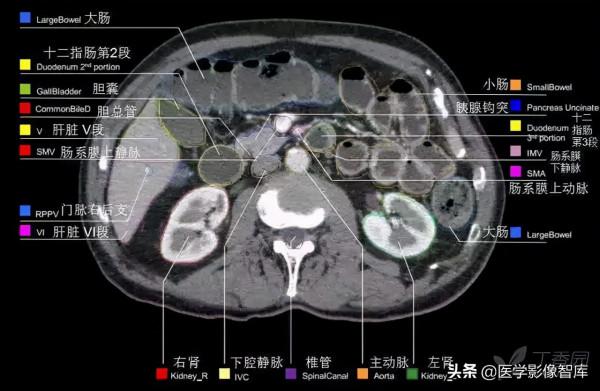

腹部CT